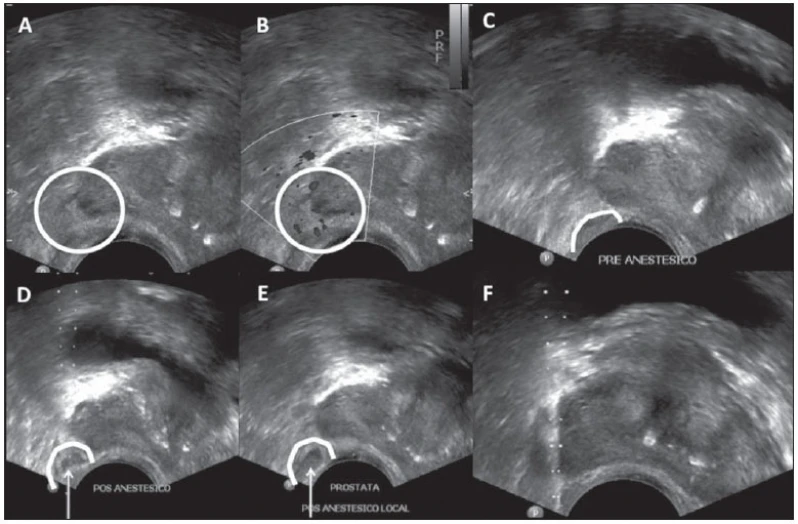

A ultrassonografia de próstata é um exame não invasivo que utiliza ondas sonoras de alta frequência para produzir imagens da próstata. É um exame importante para detectar alterações na próstata, como o aumento de tamanho, nódulos ou tumores. O exame é realizado com o paciente deitado de barriga para baixo e um gel é aplicado na região do abdômen. O médico urologista utiliza um aparelho de ultrassom para visualizar a próstata e avaliar sua estrutura. O exame é rápido e indolor, e não requer preparação especial. É recomendado para homens a partir dos 50 anos ou mais cedo em casos de histórico familiar de câncer de próstata. A DK Urologistas oferece esse exame com equipamentos modernos e profissionais especializados para garantir a precisão do diagnóstico. Agende sua consulta e cuide da sua saúde!